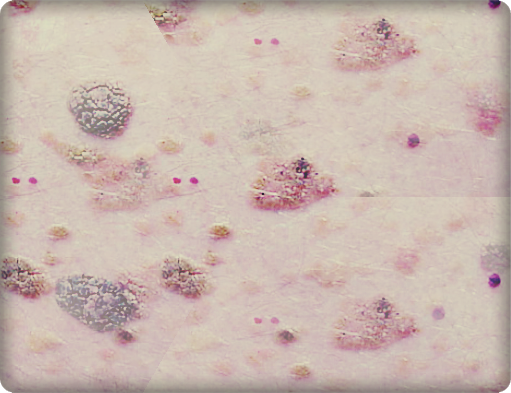

Verrucuos keratosis refers to a skin disease affecting the epidermis. Verrucous means growths resembling warts, while keratinocytes mean the growths forming on your outermost layer of the skin. The illness causes overgrowths on the skin that look like warts. The condition is also referred to as seborrheic keratosis. The only slight difference between the two is that, immediately viral warts begin to develop in seborrheic keratosis, the condition is now referred to as verrucous kerastosis. The two diseases may be similar but the causal wart develops mostly in old age. The wart is not cancerous and does not migrate to other parts of the body.

In many cases, the disease does not have any symptoms. Even a person with the illness may not present any symptoms at all. Verrucous keratosis becomes more severe later, especially when people get to the age of forty to forty five years. However, it should be noted that small hard overgrowths are found on the skin of most elderly people. As a result, not all small overgrowths may be termed as verrucous keratosis.

Clinical findings of a person with this condition are outgrowths on the trunk and face though they could also be present on other parts of the body. One could have a few lesions but in some instances, a patient has numerous lesions. The lesions will normally differ in color. They range from black to brown though those that are thinner appear paler than others. Traumatized lesions look inflamed.